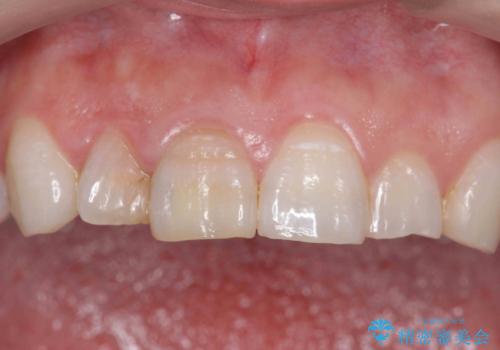

前歯の変色 セラミッククラウンによる審美性の回復

- 前歯が徐々に神経の治療を行ってから変色し、審美性の回復を求めて来院されました。

根尖に病変は見られず、根管治療は行わずに仮歯・ジルコニアクラウンを作製、装着することで審美性を回復しました。